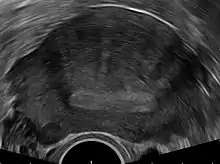

Transvaginal ultrasonography

Transvaginal ultrasonography is a cheap and readily available imaging test that is typically used early during the evaluation of gynecologic symptoms.[25] Ultrasound imaging, like MRI, does not use radiation and is safe for examination of the pelvis and female reproductive organs.[26] Overall, it is estimated that transvaginal ultrasonography has a sensitivity of 79% and specificity of 85% for the detection of adenomyosis.[11]

Common transvaginal ultrasound findings in patients with adenomyosis include the following:[9][27][28]

- globular, enlarged, and/or asymmetric uterus

- abnormally dense or especially varied density within the myometrium

- myometrial cysts - pockets of fluid within the smooth muscle of the uterus

- linear, acoustic shadowing without presence of a uterine fibroid

- echogenic linear striations - bright lines or stripes

- anterior/posterior wall asymmetry

- diffuse spread of small vessels within the myometrium

Less common findings:

- Lack of contour abnormality

- Absence of mass effect

- Ill-defined margins between a normal and abnormal myometrium

The power Doppler or Doppler ultrasonography function can be used during transvaginal ultrasonography to help differentiate adenomyomas from uterine fibroids.[25][29][30] This is because uterine fibroids typically have blood vessels circling the fibroid's capsule. In contrast, adenomyomas are characterized by widespread blood vessels within the lesion.[25] Doppler ultrasonography also serves to differentiate the static fluid within myometrial cysts from flowing blood within vessels.[25]

The junction zone (JZ), or a small distinct hormone-dependent region at the endometrial-myometrial interface, may be assessed by three-dimensional transvaginal ultrasound (3D TVUS) and MRI. Features of adenomyosis are disruption, thickening, enlargement or invasion of the junctional zone.[21]